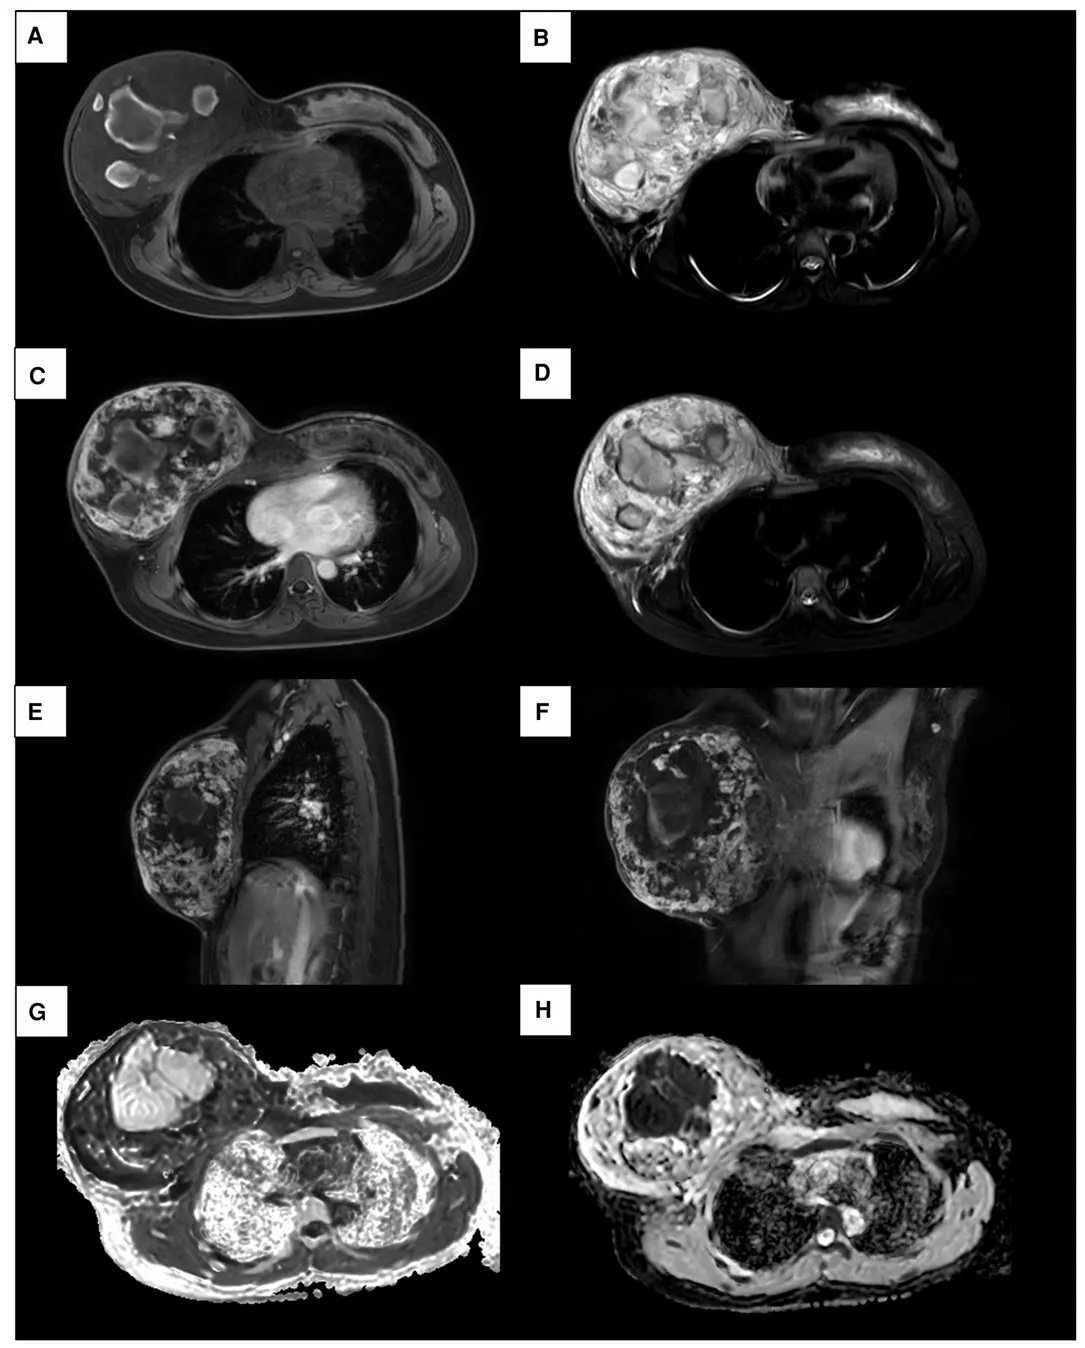

Primary breast angiosarcoma: A case report

Yu He, Liyuan Qian, Lang Chen, Yang Liu, Yanguang Wen*, Peiguo Cao*

Front Surg, 2023 (Q3, IF=1.8)